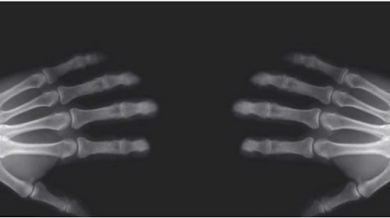

Le articolazioni sono il punto in cui le ossa si incontrano e si uniscono. Tutte le articolazioni sono circondate e protette dalla capsula articolare che contiene un lubrificante naturale chiamato liquido sinoviale, necessario per il corretto movimento delle articolazioni.

Questo liquido influisce nel rumore dello schiocco delle ossa perché contiene aria. Quando si scrocchiano le dita, le articolazioni si separano ed aumenta lo spazio all’interno della capsula articolare, di conseguenza i gas disciolti formano bollicine per occupare il nuovo spazio che si è creato.

Facendo forza sulle nocche, le bollicine formatesi si liberano velocemente ed è a questo punto che si sente il caratteristico “croc”.

Dopo questo suono, non è possibile ripetere subito il gesto perché le articolazioni devono prima tornare alle loro dimensioni normali e i gas devono disciogliersi nel liquido. Trascorsi 15 minuti, è possibile che le dita rifacciano questo rumore se le scrocchiate.